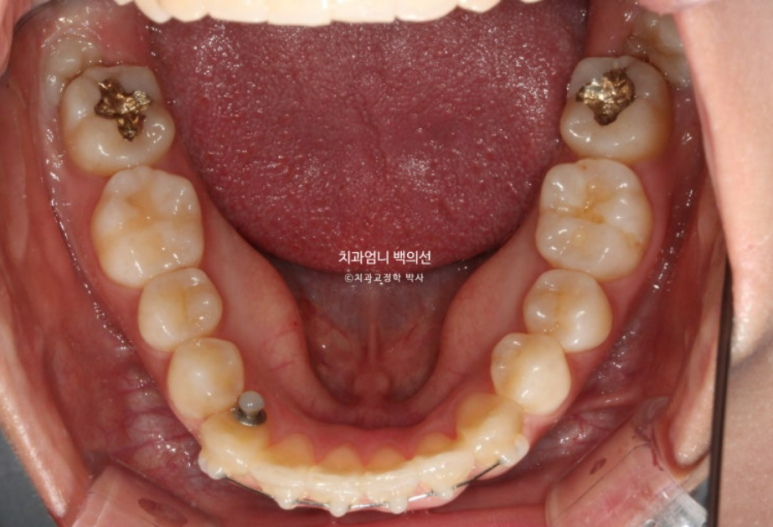

치료시작 9개읠째 모습입니다.

앞니 사이 미세한 틈을 없애기 위해 파워체인 고무를 걸고

사진에 보이는 고리끼리는 환자분이 스스로 뺐다 꼈다 하는 고무줄을 걸고 중심선과 좌우 교합까지 마춥니다.

그러다보니 어느덧 9개월이 흘렀습니다.

MTA 장치는 송곳니부터 송곳니까지 앞니에만 붙여서 배열을 진행했고 나머지 작은어금니와 큰어금니는 움직이지 않았습니다

유지장치까지 붙은 모습입니다. 총 치료기간은 9개월입니다.